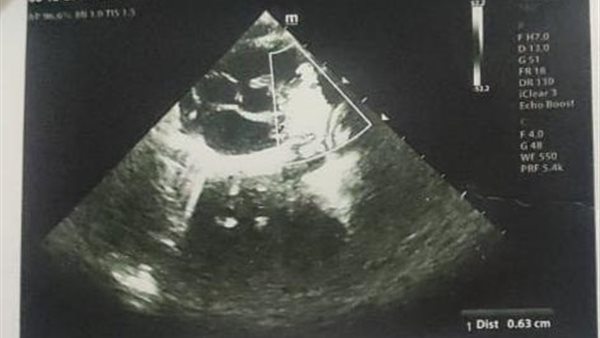

استغاث والدة الرضيعة ماريا بطرس، لإنقاذ ابنته المصابة بعيب خلقي في القلب، والتي تحتاج إلى قسطرة غير جراحية، لغلق وصلة شريانية بالقلب عن طريق سدادة.

وأضاف بطرس، أثناء فترة العلاج قام الأطباء بعمل الفحوصات للاطمئنان على صحة الطفلة، وعندها اكتشفوا أنها تعاني من عيب خلقي في القلب، وعندها أقر الأطباء في معهد القلب من ضرورة خضوع الطفلة لقسطرة غير جراحية، باستخدام جهاز وصلة شريانية وسدادة لعلاج هذا العيب الخلقي، وذلك وفقًا لتقرير طبي صدر يوم 1 من ديسمبر 2022.